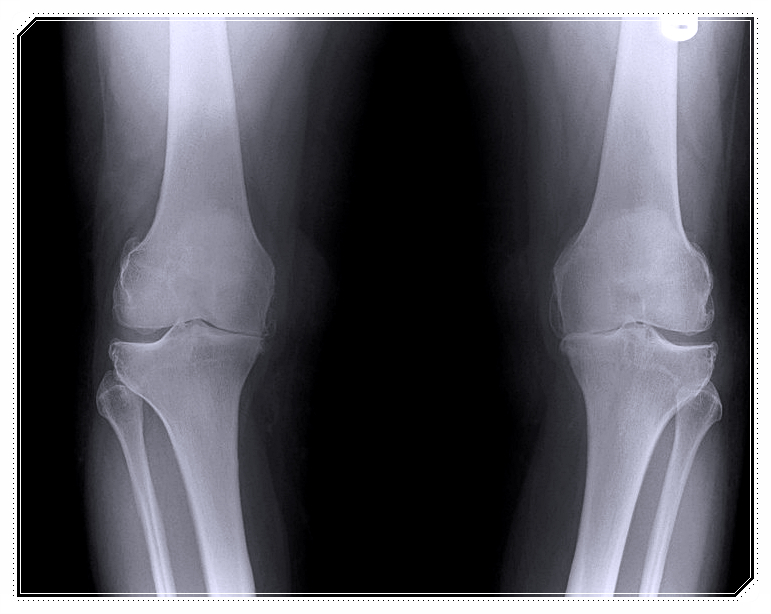

의사와 한의사가 협진하여 엑스레이 등을 통해 구조적 문제를 확인합니다.

이러한 증상은 무릎 관절이 보내는 구조적 신호일 수 있습니다.